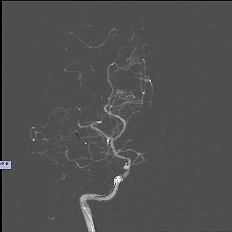

CTA

image.png  image.png

DSA

8月25日.gif